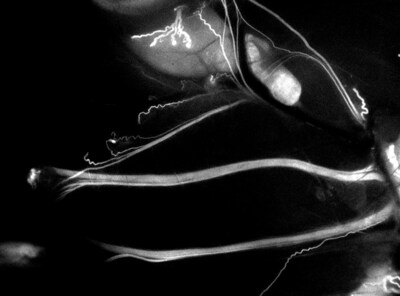

A new roadmap to surgery - IND-approved LGW16-03, also known as NerveTrace Dx, enables real-time visualization of complex nerve anatomy so surgeons can cut by color to spare critical nerves and improve patient outcomes.

LGW16-03 is designed to selectively bind peripheral nerves and emit a near-infrared fluorescent signal, allowing surgeons to visualize critical nerve structures in real time during surgery even when buried beneath tissues. Accidental nerve injury remains a significant and under-addressed cause of surgical complications across procedures such as prostatectomy, orthopedic surgery, colorectal surgery, and head and neck surgery. These injuries can result in chronic pain, incontinence, numbness, sexual dysfunction, voice loss, or other permanent loss of function – outcomes that profoundly impact patients' quality of life.